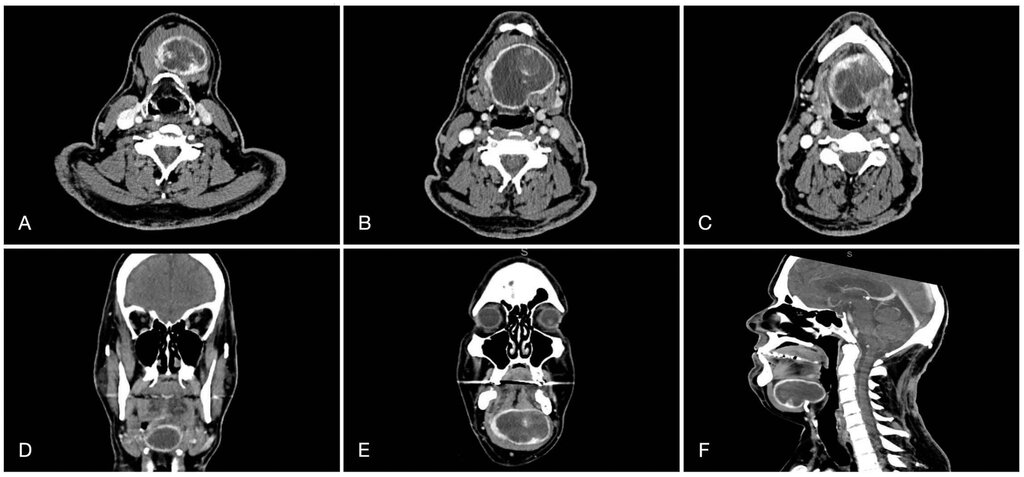

In der durchgeführten Orthopantomografie zeigten sich multiple nicht erhaltungswürdige Zähne, jedoch ohne eindeutigen dentalen Fokus. Zur weiteren Diagnostik führten wir eine Computertomografie durch. Dabei zeigte sich eine scharf abgrenzbare, randständig deutlich Kontrastmittel-anreichernde, insgesamt inhomogen kontrastierte Raumforderung submental bis suprahyoidal von circa 6,9 cm x 5,1 cm x 3,9 cm Größe. Es gab keinen Hinweis auf lokal destruierendes Wachstum oder Filiarisierung. Wie schon in der auswärtig durchgeführten Schilddrüsensonografie und -szintigrafie war auch in der Computertomografie das Schilddrüsenparenchym kaum abgrenzbar.